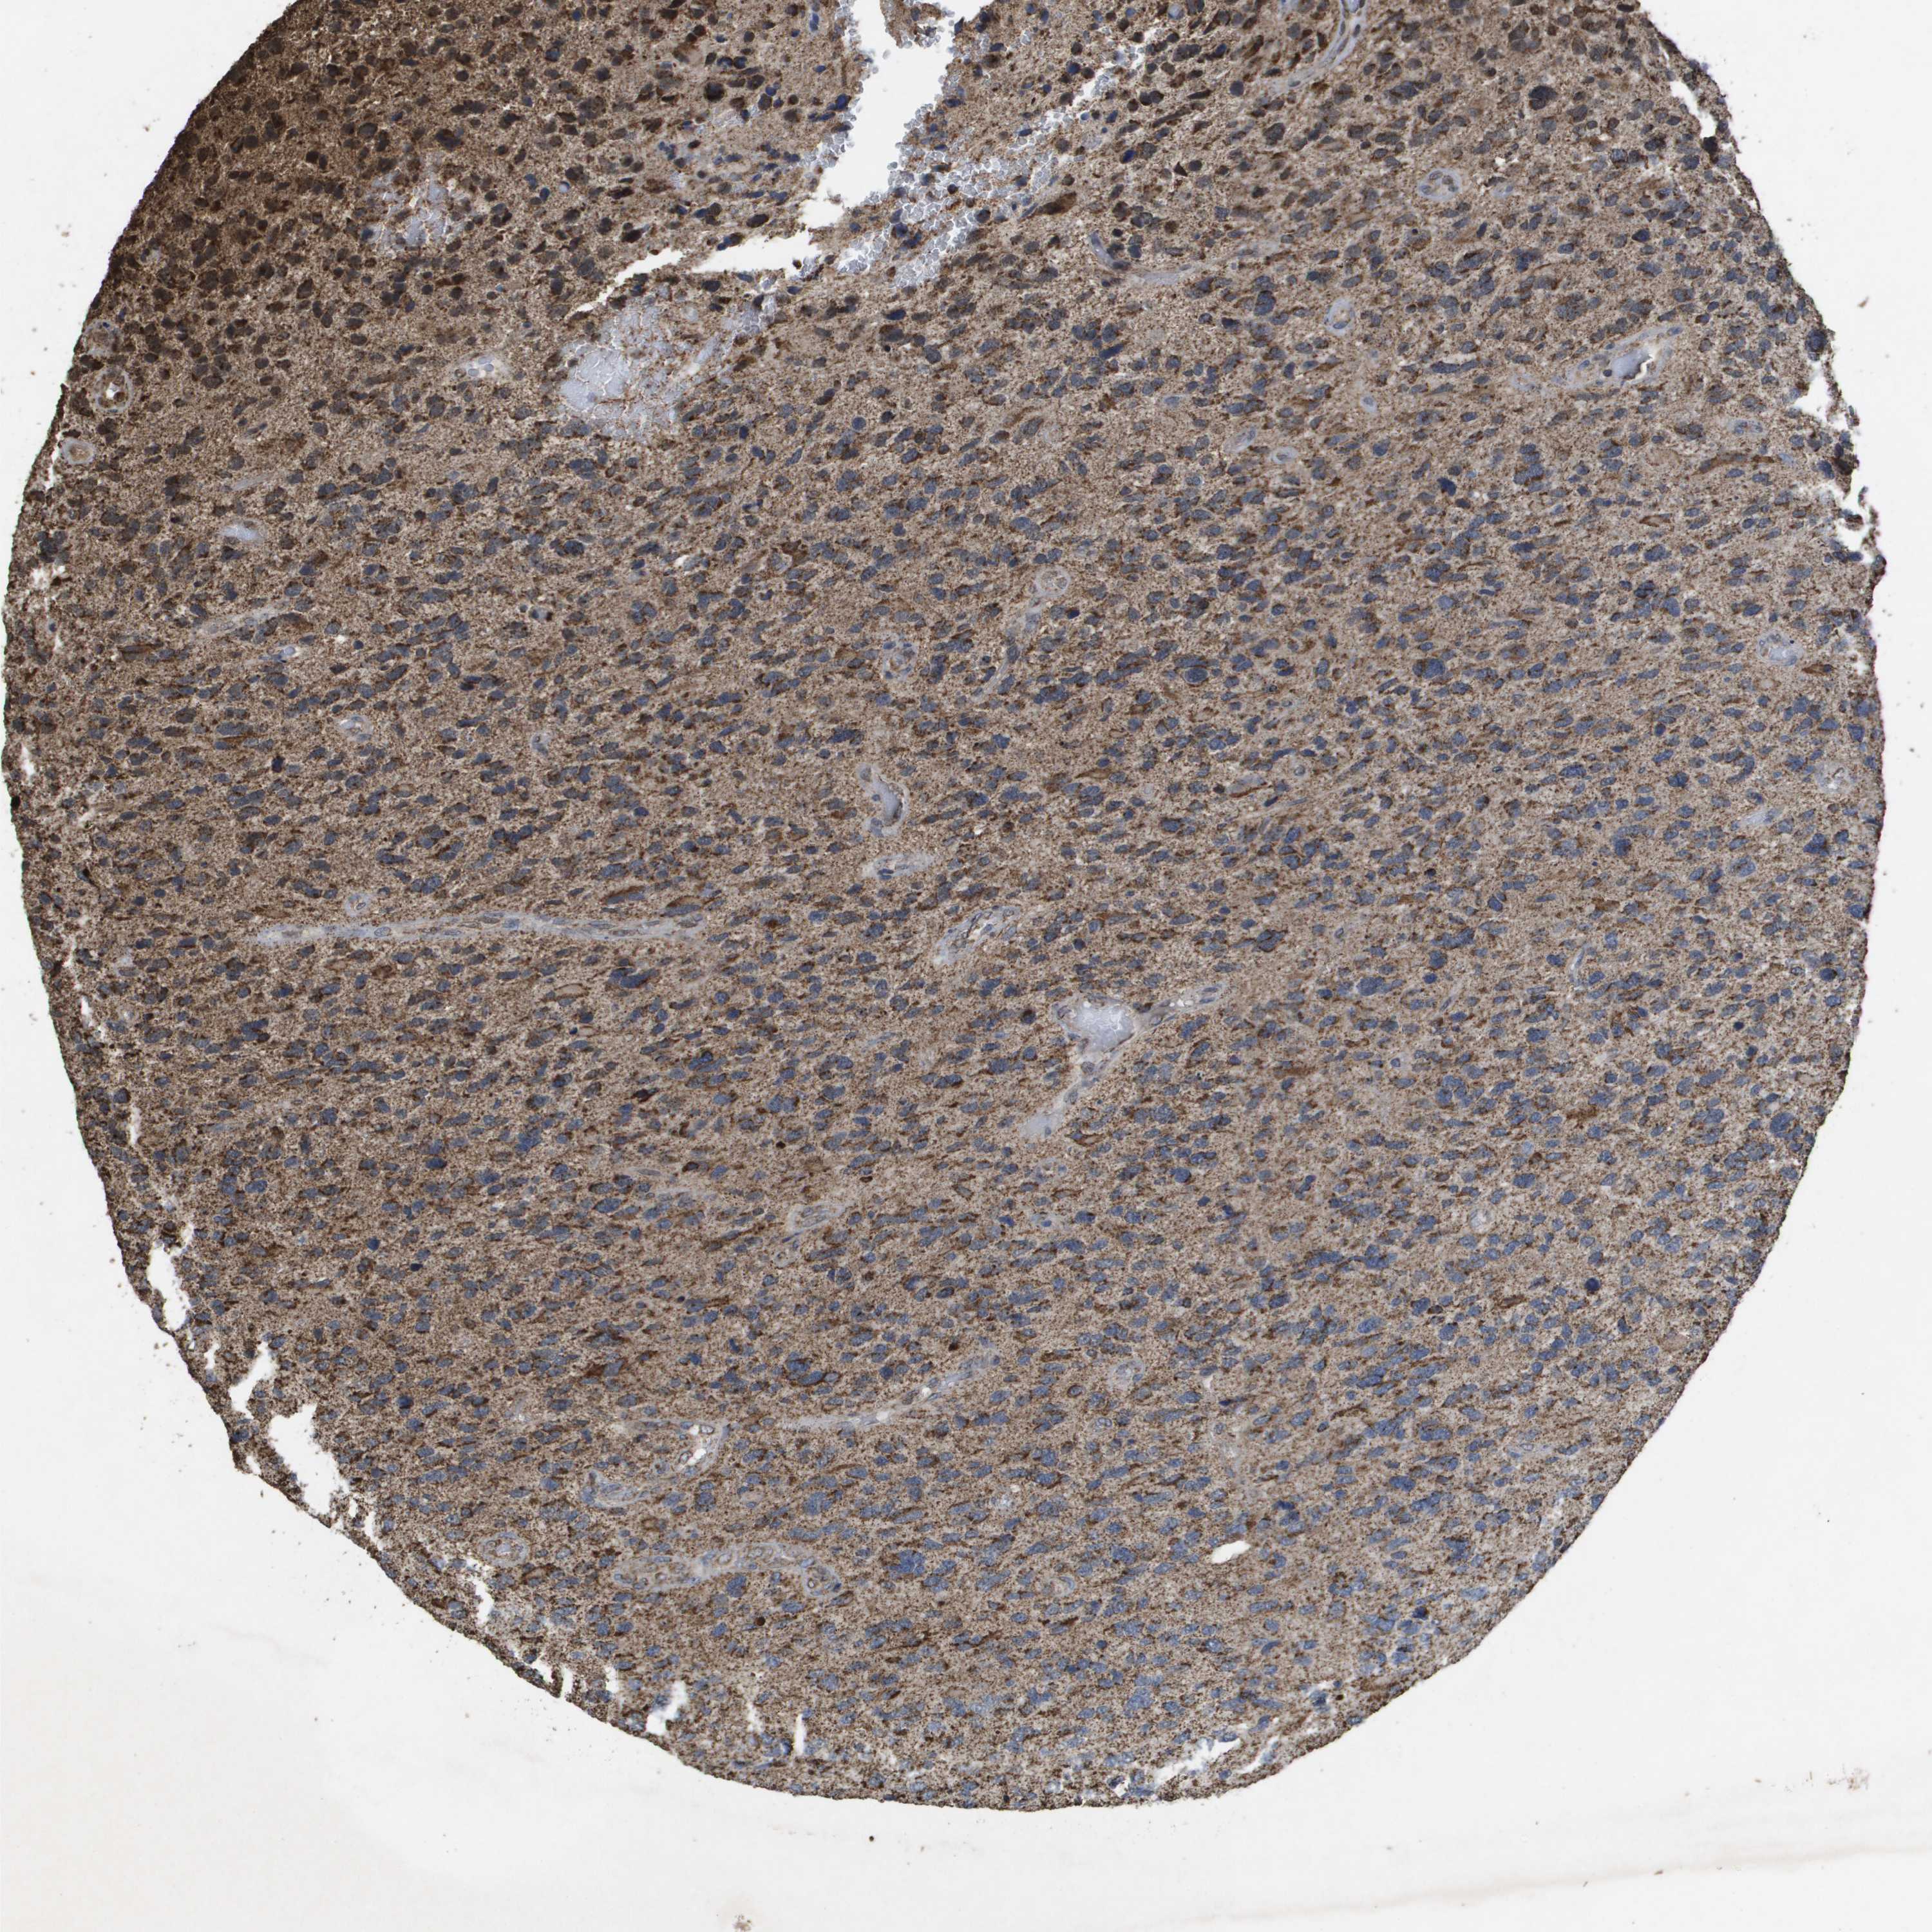

GLIOMA - Protein expressioni

A mouse-over function shows sample information and annotation data. Click on an image to view it in a full screen mode. Samples can be filtered based on level of antibody staining by selecting one or several of the following categories: high, medium, low and not detected. The assay and annotation is described here.

Note that samples used for immunohistochemistry by the Human Protein Atlas do not correspond to samples in the TCGA dataset.

Antibody stainingi

Antibody staining in the annotated cell types in the current human tissue is reported as not detected, low, medium, or high, based on conventional immunohistochemistry profiling in selected tissues. This score is based on the combination of the staining intensity and fraction of stained cells.

Each image is clickable and will lead to virtual microscopy that enables deeper exploration of all samples and also displays staining intensity scores, fraction scores and subcellular localization as well as patient and tissue information for each sample.

Antibody HPA038755

Antibody HPA048272

Antibody CAB017366

Staining

High

Medium

Low

Not detected

Intensity

Strong

Moderate

Weak

Negative

Quantity

>75%

75%-25%

<25%

None

Location

Nuclear

Cytoplasmic/membranous

Cytoplasmic/membranous,nuclear

Glioma, malignant, High grade

Glioma, malignant, Low grade

Glioblastoma, NOS